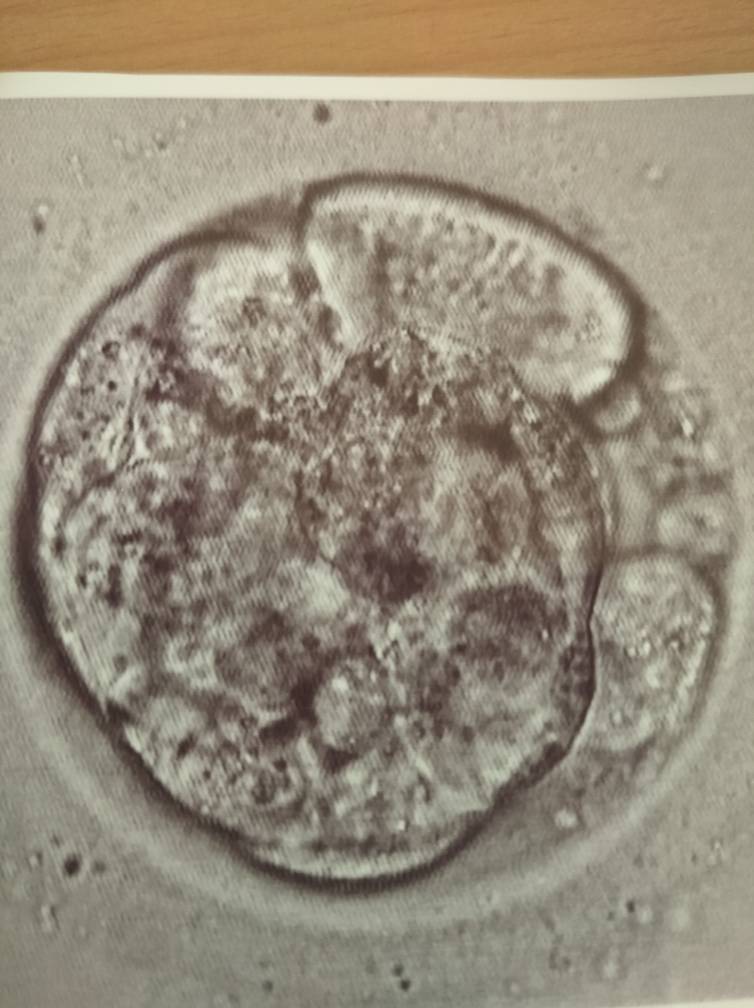

Wygląd za duzo nie mówi, powinnas miec napisaną kategorię w dokumentacji.Ktoś może się na tym zna? [emoji16]Zobacz załącznik 1174265

Podobno wczesna blastocysta

Wczesna czyli 1 albo 2.Ktoś może się na tym zna? [emoji16]Zobacz załącznik 1174265